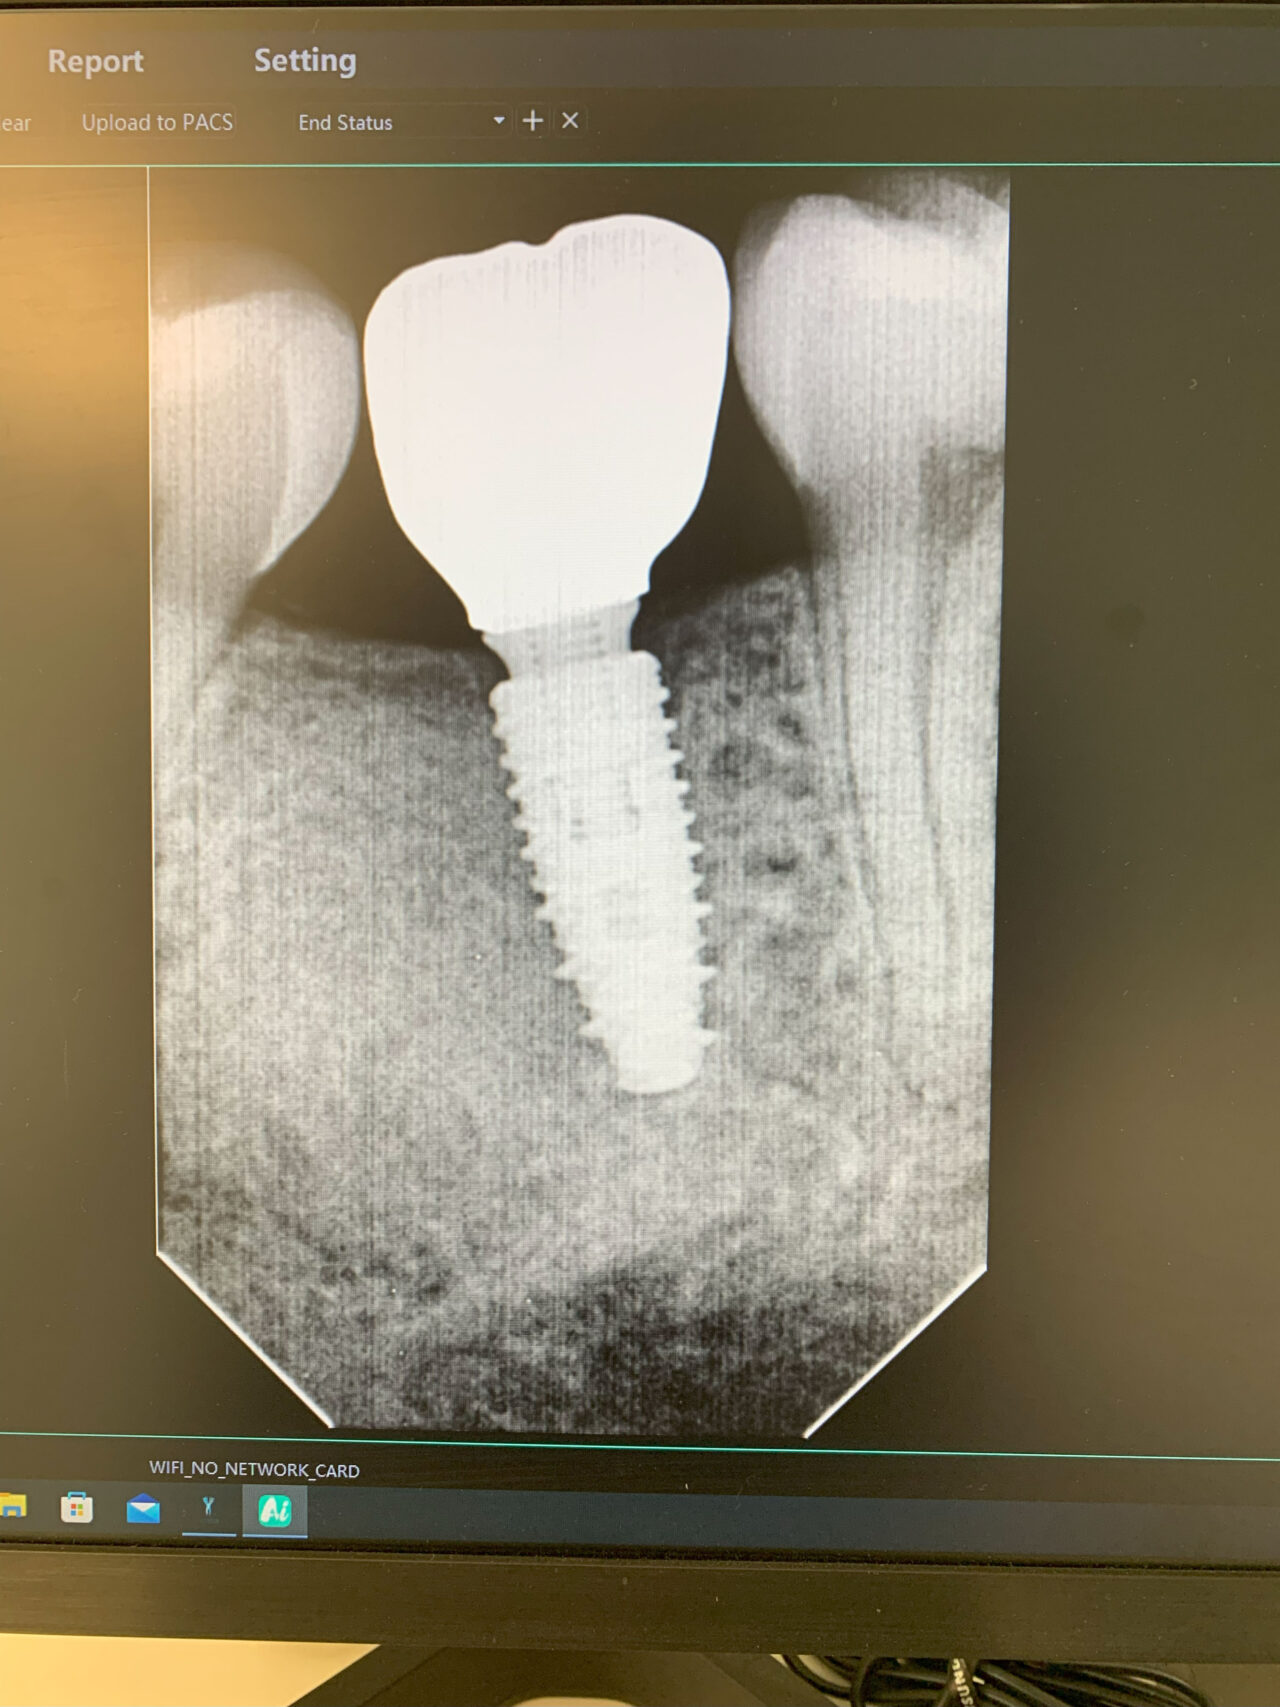

L’Implantologie Orale constitue un ensemble de techniques dentaires visant à remplacer une ou plusieurs dents manquantes par des implants solidement ancrés dans l’os de la mâchoire. Ce processus implique un large éventail de traitements ou de procédures nécessitant une préparation méthodique, afin de garantir la stabilité et la longévité de l’implant. Il comprend notamment des étapes permettant de favoriser une parfaite intégration de l’implant dans la structure osseuse.